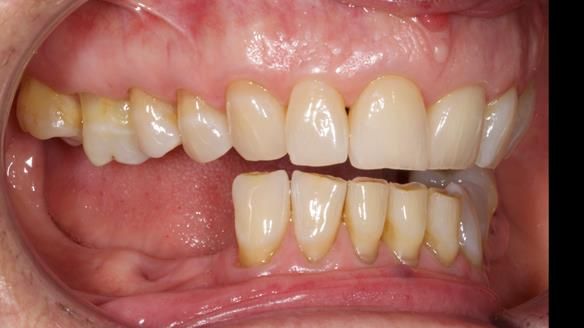

Welcome to Newsletter 61. In this edition, I walk through the process of creating and fitting a metal based lower partial denture for Joyce, a fit and healthy 76 -year-old woman.This issue shows the complete protocol workflow for achieving an exceptionally well-fitted and aesthetically good RPD.

Joyce's Case Presentation 61

Welcome to Newsletter 61. In this edition, I walk through the process of creating and fitting a metal based lower partial denture for Joyce, a fit and healthy 76 -year-old woman.

Joyce self-referred to me for specialist prosthodontics.

The missing lower right teeth to be replaced with a metal based partial denture.

The detailed clinical situation and treatment process are outlined below, with clinical work provided by me and technical work by Rowan Garstang. The treatment spanned six visits for denture fitting and one review.